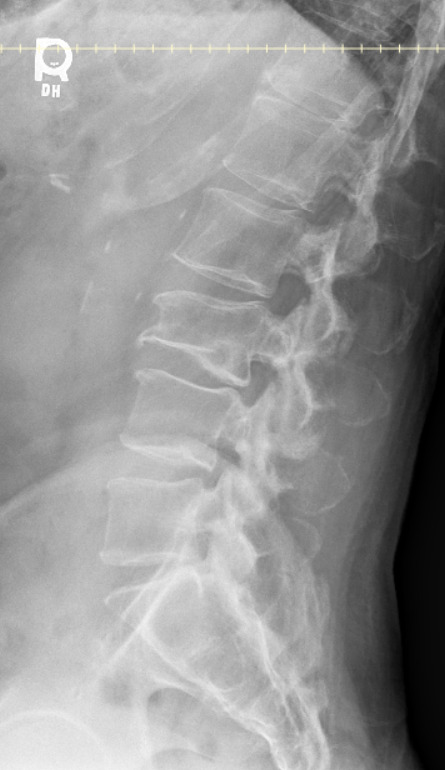

Radiographic examination of the cervical and lumbar spine identified adequate bone density, (decreased bone density cannot be identified on plain radiographs until more than 30-50% of bone mass has been lost3), cervical, lower thoracic and lumbar disc degeneration, and cervical and lumbar zygapophyseal osteoarthrosis.

Approximately 10 weeks later the patient reported injury to the low back while carrying a large, heavy object and stepping down, resulting in moderate, non-radiating pain with both rest and activity. Radiographic examination of the lumbar spine revealed a compression fracture of the inferior aspect of L3 with step defect, possibly acute, and ununited left L2 and L3 transverse processes, age indeterminate. The patient was referred for DEXA bone density examination and cross-sectional imaging (CT) to further evaluate the extent of the L3 compression fracture.

Chiropractic care using Thompson drops in unaffected spinal regions continued for the next 5 weeks. After a 7-month absence from care, the patient returned reporting midline and centrally worsening non-radiating low back pain after a fall on his back and buttocks approximately 3-4 months prior in his bathroom. He was seen by his medical doctor prior to the treatment visit for this incident and had been referred to physical therapy. He denied head injury, fracture, loss of consciousness, saddle paresthesia or changes with bowel and bladder function. Radiographic examination of the lumbar spine demonstrated superior and inferior endplate fractures of the T12 vertebral body with 60% vertical loss of height not evident on previous examination. Osteoporosis was reported at this time. Examination with CT and MRI were recommended for further characterization of the T12 compression fracture due to the severity of radiographic presentation. The patient was referred to his primary care physician for co-management and the provider was contacted directly due to the loss of vertebral body height (see Table 1 for overview of progression of care).